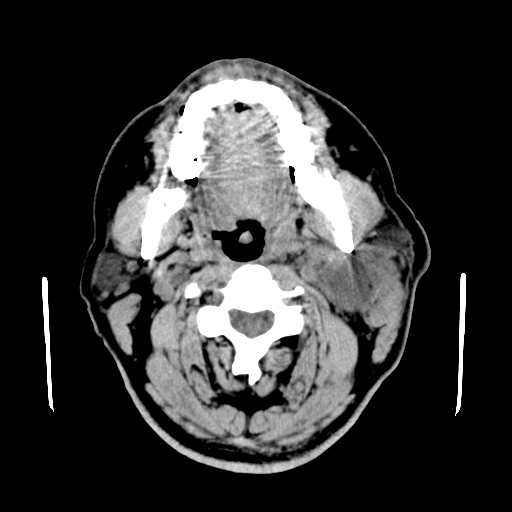

以下是引用卜一在2007-8-6 21:23:00的发言:[br]定位:左侧胸锁乳突肌内侧 颌下腺下后方。特征:弥漫性生长 软组织密度肿块,界限不清,内隐约见低密度坏死。考虑:神经源性肿瘤或血管源性肿瘤。

以下是引用wangzhanshuang在2007-8-6 21:08:00的发言:[br]腮腺混合瘤